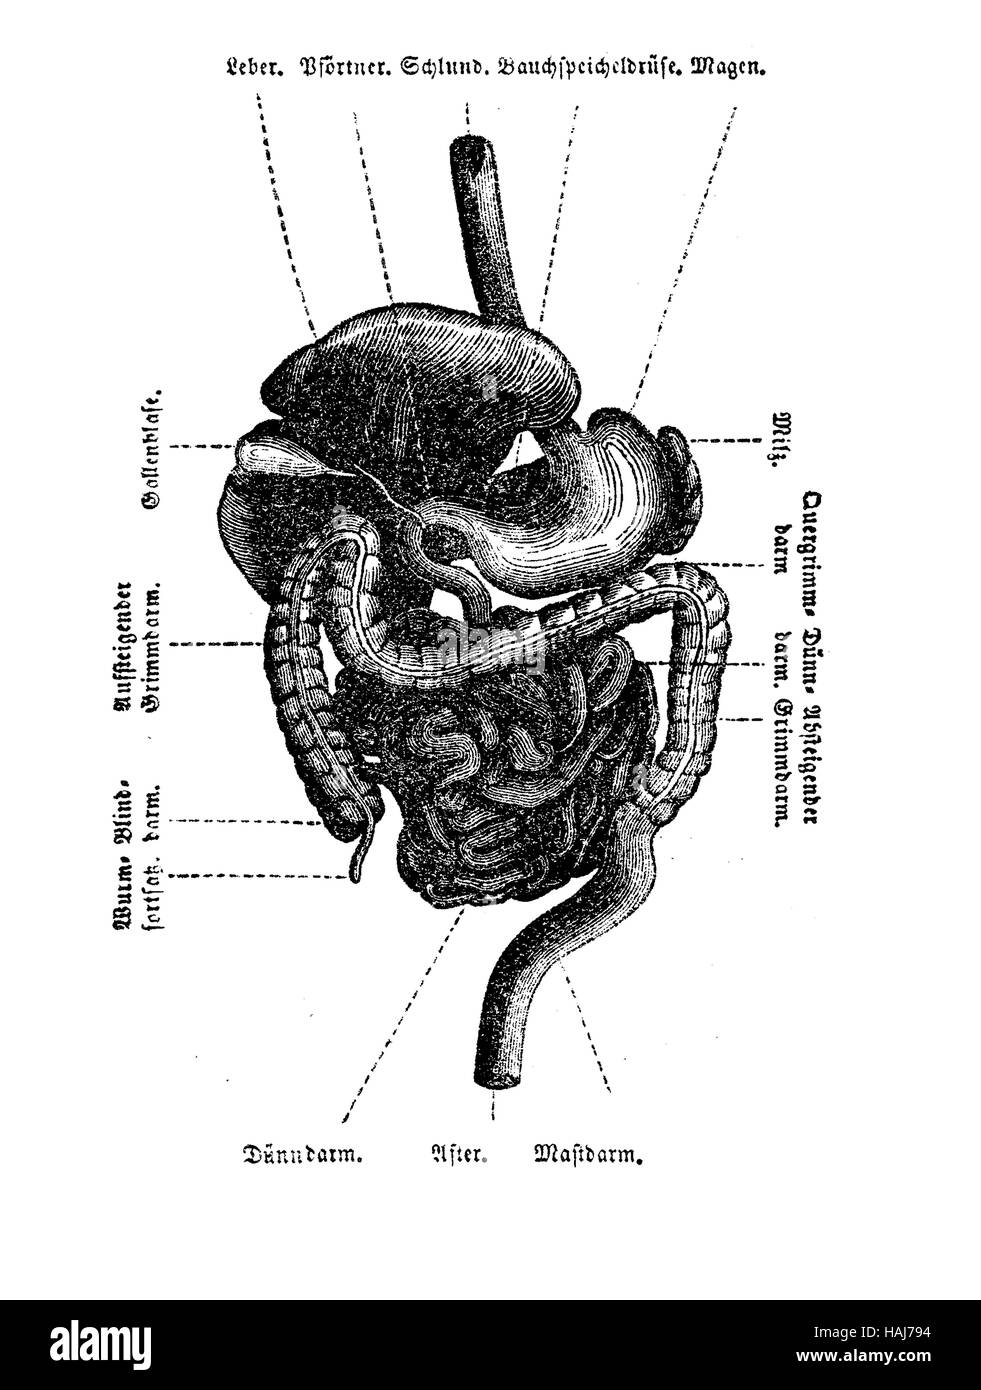

Anatomy, abdomen cavity organs table, engraving XIX century Stock Photohttps://www.alamy.com/image-license-details/?v=1https://www.alamy.com/stock-photo-anatomy-abdomen-cavity-organs-table-engraving-xix-century-127020016.html

Anatomy, abdomen cavity organs table, engraving XIX century Stock Photohttps://www.alamy.com/image-license-details/?v=1https://www.alamy.com/stock-photo-anatomy-abdomen-cavity-organs-table-engraving-xix-century-127020016.htmlRFHAJ794–Anatomy, abdomen cavity organs table, engraving XIX century